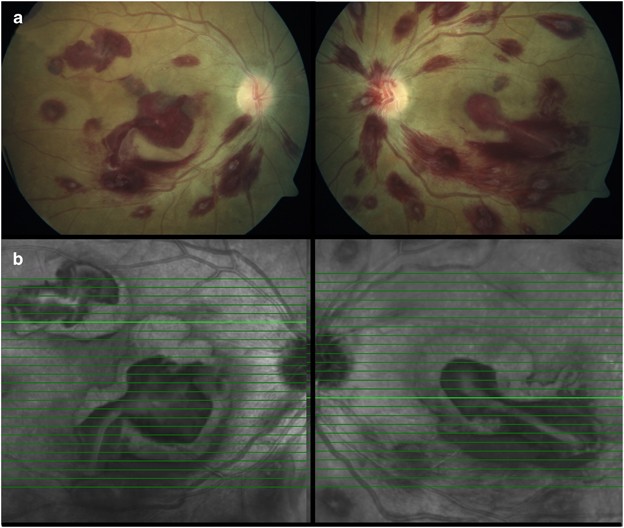

Leukemic Retinopathy

Multiple Roth S Spots On The Fundus Of A Patient With Acute Leukemia Download Scientific Diagram